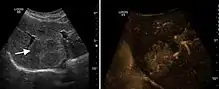

Benign focal nodular hyperplasia (CEUS). Gray scale examination (left) detects the lesion. CEUS examination (right) allows characterization of tumor nature based on central contrast enhancement and centrifugal dispersion.

It is a tumor developed secondary to a circulatory abnormality with abundant arterial vessels having a characteristic location in the center of the tumor, within a fibrotic scar. A radial vessels network develops from this level with peripheral orientation. The tumor's circulatory bed is rich in microcirculatory and portal venous elements. The incidence is higher in younger women and tumor development is accelerated by oral contraceptives intake. 2D ultrasound appearance is a fairly well-defined mass, with variable sizes, usually single, solid consistency with inhomogeneous structure. Rarely the central scar can be distinguished. Spectral Doppler examination detects central arterial vessels and CFM exploration reveals their radial position. CEUS examination shows central tumor filling of the circulatory bed during arterial phase and completely enhancement during portal venous phase. During this phase the center of the lesion becomes hypoechoic, enhancing the tumor scar. During the late phase the tumor remains isoechoic to the liver, which strengthens the diagnosis of benign lesion.

Liver abscess (2D and CEUS). 2D Examination reveals the fluid nature of the mass and imprecise delineation. CEUS examination shows congestion in the surrounding liver parenchyma and excludes a vascular tumor.

Liver abscess have heteromorphic ultrasound appearance, the most typical being that of a mass with irregular shapes, fringed, with fluid or semifluid content, with or without air inside. Doppler examination shows the lack of vessels within the lesion. CEUS exploration shows hyperenhancement during arterial phase close to the lesion, this being suggestive of a liver parenchymal hyperemia. During venous and sinusoidal phase the pattern is hypoechoic, and the central fluid is contrast enhanced. CEUS examination is useful because it confirms the clinical suspicion of abscess. In addition, it allows for an accurate measurement of the collection size and an indication regarding its topography inside the liver (lobe, segment).